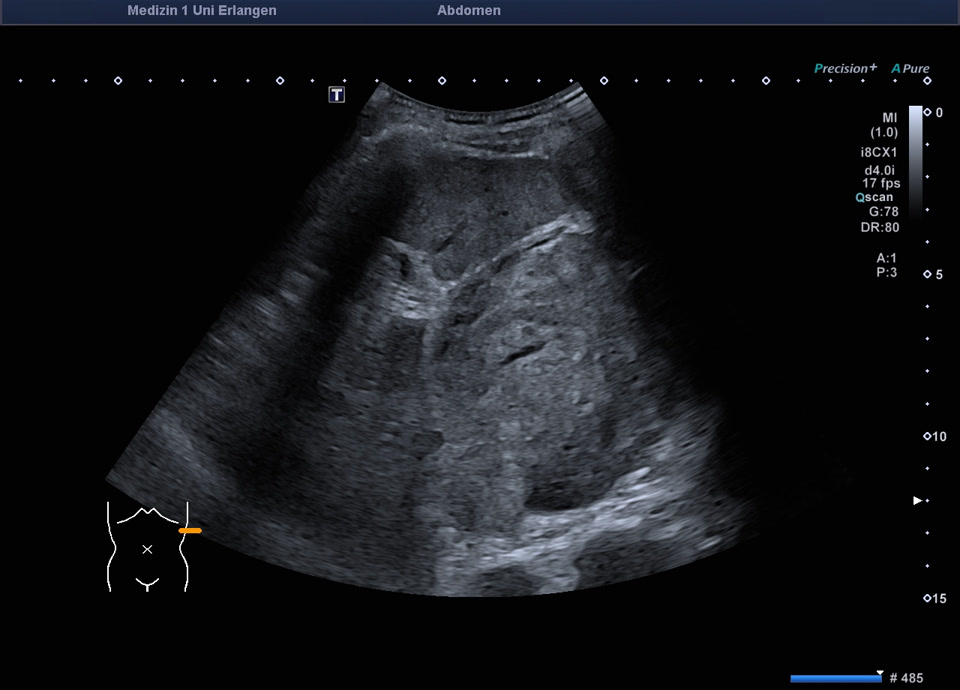

47-year-old patient presents to the emergency department with flank pain. Ultrasound shows a large, inhomogeneous, sharply defined mass in the left adrenal gland. A blood sample (including metanephrines) and a puncture (endosonographic access) are initiated for further clarification. Histologically adrenal cancer